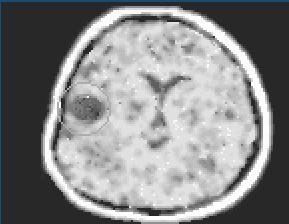

B.b CAT (Computer Assisted Tomography)

CTčko je špecializovaný roentgenová technika ktorá

zmapuje vnútro paciantovho tela krížom krážom. Počítač následne

vyhodnotí hustotu tkání a orgánov v tele a ukáže na obrázku. Pretože používa

jód nie je vhodný pre pacientov s alergiou na jód. V takom prípade použi

MRI.

Takto vyzerá CT mozgu v normálu. Krásna biela buchta bez ničoho.

Čierna výplň lokalizovaná na okrajovej časti cerebra - to je tumor, čiže nádor.